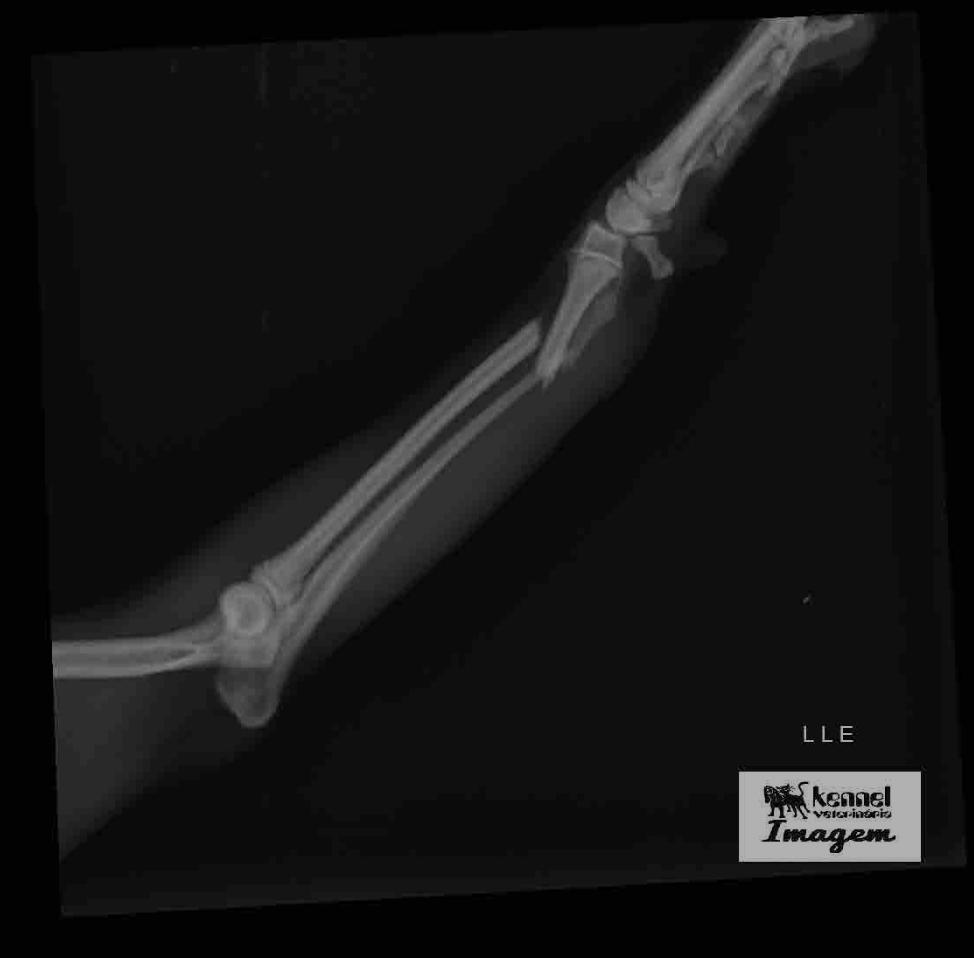

A tutora contou que, logo após o acidente, que aconteceu na quinta-feira (1°), o animal foi atendido por médicos veterinários, que falaram da necessidade da cirurgia. “Ele caiu e quebrou a patinha. Levei na emergência veterinária 24 horas e cobraram R$ 600 para tirar raio-X e colocar uma tala de imobilização. Me orientaram que ele precisaria de uma cirurgia ortopédica, procurei em todos os lugares e só encontrei de dois mil reais para cima”, explicou.